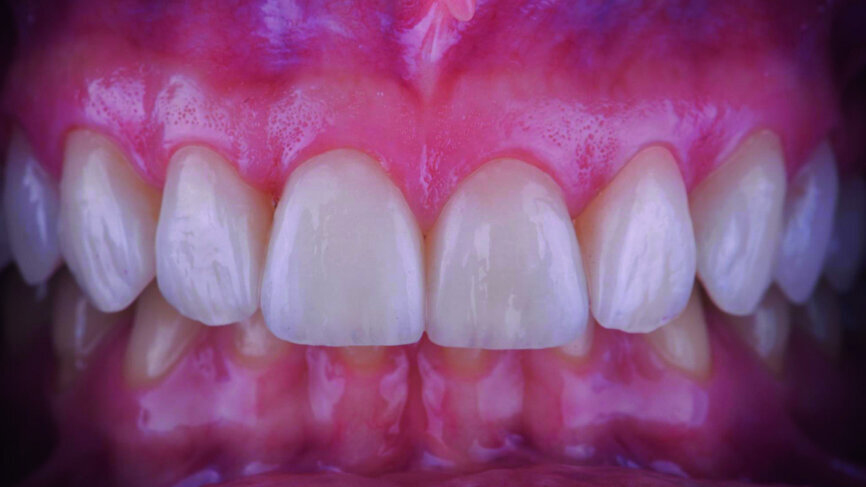

Fig. 17a: Final outcome one week later.

Fig. 17b: Final outcome one week later, frontal view.